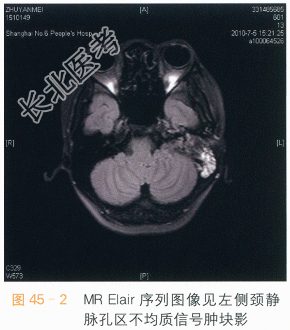

读片分析:颈静脉球瘤是化学感受器瘤的一种,临床上无特异性体征,常常因为肿瘤侵犯到颞骨和耳道,出现相应症状来就诊,颈静脉球瘤发生于颅底颈静脉孔区域,它系富血供肿瘤。颈静脉球瘤CT扫描检查特征性表现是颈静脉孔的扩大,常伴有周围颞骨的骨质破坏和吸收,肿瘤常侵及内耳、中耳和外耳道(见图45-1)。MR检查冠状面图像可见肿瘤沿颈静脉孔向下呈锥形生长,边界清楚、有包膜,可有明显强化(见图45-3、图45-4)。在MRI成像上有时还可见到具有经典的影像学特征──“椒盐征”,这时瘤体内流空的血管低信号断面与肿瘤实质部呈现的高信号相间,如同花椒撒在白盐中(见图45-2)。